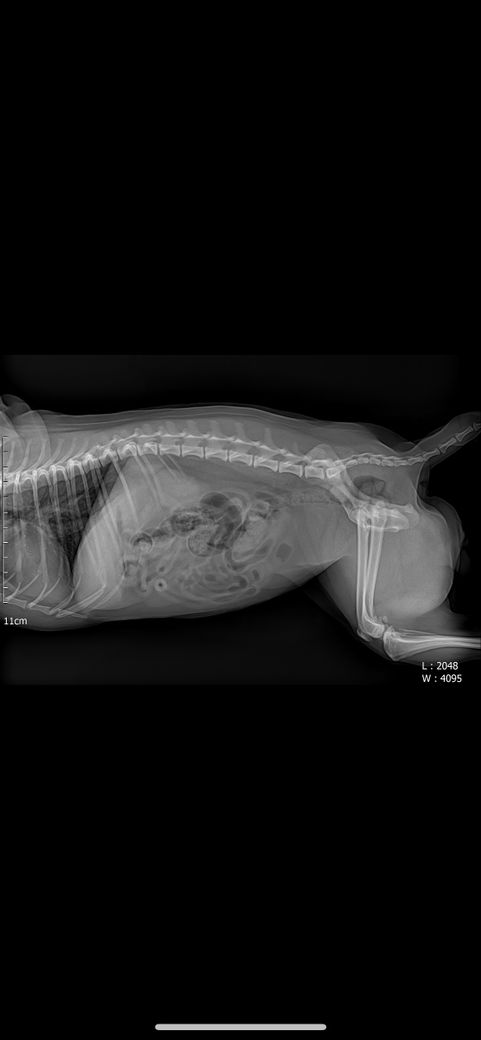

강아지 엑스레이에 문제점 있는지 봐주세요

강아지 엑스레이 문제 되는 곳 있는지 봐주세요 심장 크기랑 간이나 등등 문제 되는 곳이 있는지 궁금합니다 병원에선 문제 되는 곳 없다고 하시긴 했는데 조금 더 확실하게 알고 싶어서요

안녕하세요. 박창민 수의사입니다. 크게 문제되는 부분은 없는 거 같습니다. 또한, 엑스레이로는 정말 제한적인 정보만 얻을 수 있습니다. 더 많은 정보를 원하시면, 초음파 검사를 받으셔야 합니다. 감사합니다.

주치의의 판단이 옳은것으로 보입니다. 다만 좌측 슬개골의 내측 변위 양상 즉, 슬개골 탈구 상태가 있으니 이 부분에 대해 상담받으시고 수술 결정하시기 바랍니다.